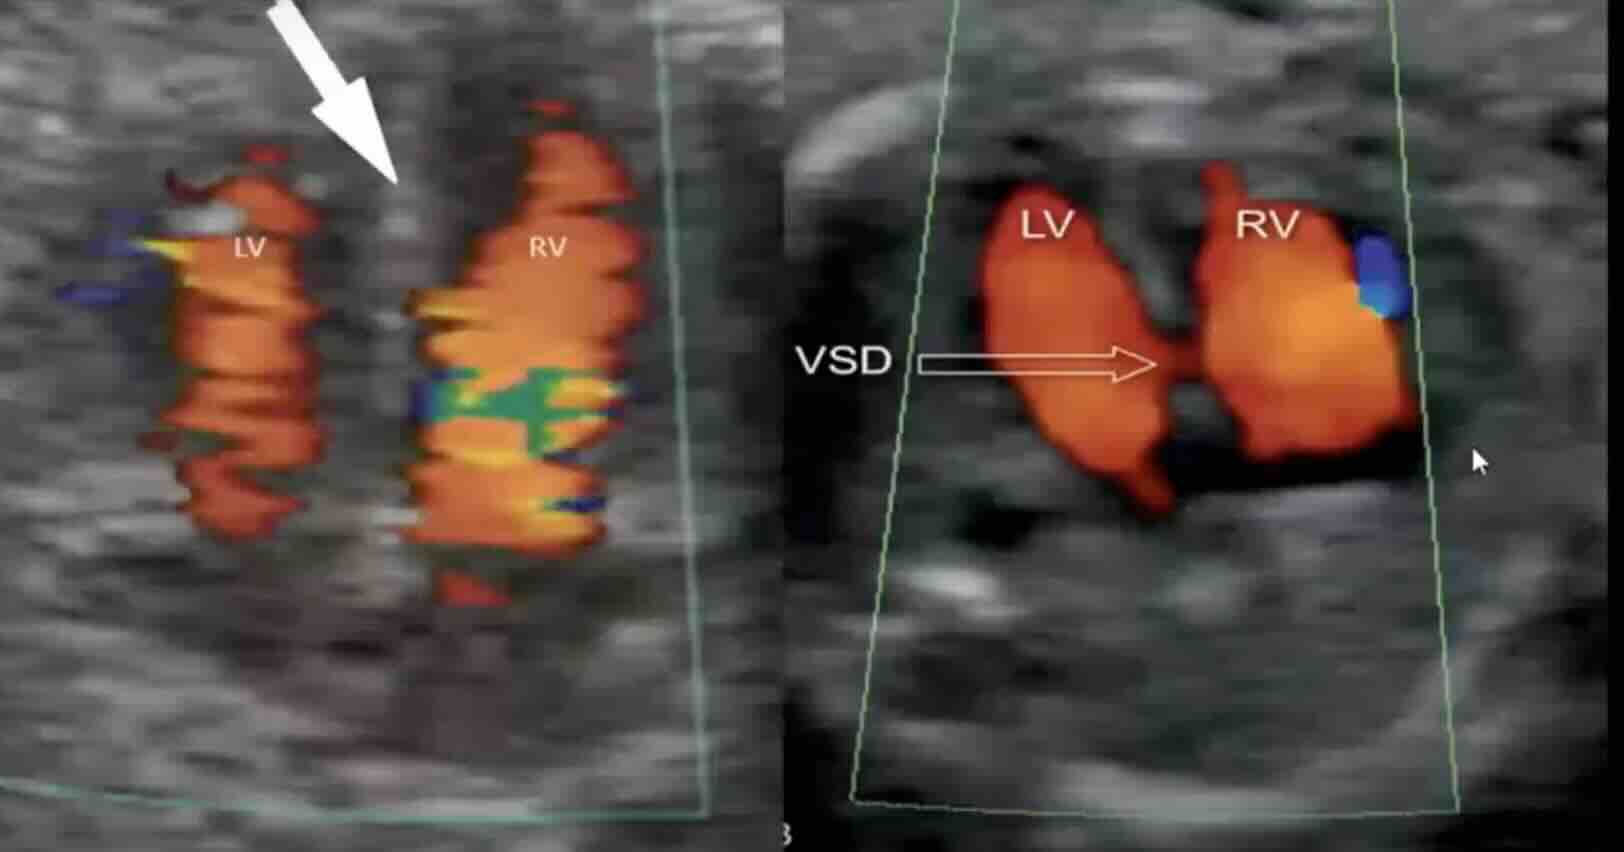

6. Ultrason Kriterleri: Kesin Düşük Nasıl Anlaşılır?

Erken gebelik kaybında en kesin bilgi ultrason ile elde edilir. Aşağıdaki bulgular kesin düşük tanısı koydurur:

Kesin Düşük Bulguları:

CRL (baş-popo mesafesi) ≥7 mm olduğu halde kalp atışı yok

Gebelik kesesi ≥25 mm olduğu halde embriyo yok (boş gebelik)

Embriyo varken kalp atışı daha önce varken sonra durmuşsa

İki ultrason kontrolü arasında embriyo hiç büyümemişse

Şüpheli Bulgular (Kesin Değil, Tekrar Beklenir):

Kesenin beklenenden küçük olması

Embriyonun küçüklüğü

Kalp atışının yavaş olması (dakikada <100)

Kesenin şekil bozukluğu